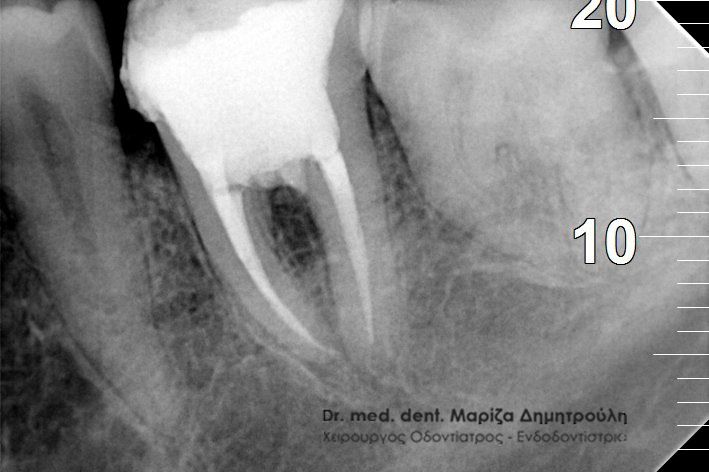

Στο συγκεκριμένο περιστατικό είχε πραγματοποιηθεί από συνάδελφο απονεύρωση δοντιού και ο ασθενής αναφέρει τις έντονες ενοχλήσεις που του προκαλεί το δόντι το τελευταίο τρίμηνο. Η ακτινογραφία αποκάλυψε αφενός το μικρό μήκος της απονεύρωσης στην εγγύς ρίζα του δοντιού και αφετέρου την ύπαρξη περιακρορριζικής αλλοίωσης στην άπω ρίζα δοντιού, η οποία έχει τη μορφή μιας μαύρης σαφώς περιγεγραμμένης σκιάς. Η εμφάνιση της αλλοίωσης αυτής σημαίνει οτι το δόντι έχει φλεγμονή, η οποία πρέπει να αντιμετωπιστεί.

ΠΡΙΝ ΜΕΤΑ

Στον παραπάνω ασθενή έγινε επανάληψη απονεύρωσης και εντοπίστηκε και τέταρτος ριζικός σωλήνας, ο οποίος δεν είχε βρεθεί στην πρώτη ενδοδοντική θεραπεία.

Η ασθενής παραπονιόταν για συνεχή πόνο στο συγκεκριμένο δόντι, το οποίο είχε απονευρωθεί πριν χρόνια. Μετά από τη λήψη ακτινογραφίας διαπιστώθηκε οτι στην πρώτη ενδοδοντική θεραπεία δε είχε μετρηθεί σωστά το μήκος της ρίζας του δοντιού. Μετά την επανάληψη της απονεύρωσης το δόντι καθαρίστηκε και εμφράχθηκε σε όλος το μήκος της ρίζας, όπως δείχνει και η δεξιά αντινογραφία.

Διαπίστωση της διάτρησης

Εντοπισμός του τρίτου ριζικού σωλήνα

Ολοκληρωμένη απονεύρωση

Η ασθενής απευθύνθηκε στο ιατρείο γιατί το συγκεκριμένο δόντι έδινε συμπτώματα πόνου παρόλο που είχε ξεκινήσει η διαδικασία της απονεύρωσης. Μετά την κλινική εξέταση του δοντιού διαπιστώθηκε διάτρηση μεταξύ των ριζικών σωλήνων του δοντιού, η οποία επιβεβαιώθηκε με τη λήψη ακτινογραφίας (πρώτη ακτινογραφία). Το σημείο της διάτρησης εμφράχθηκε με ειδικό υλικό. Στη συνέχεια εντοπίστηκε ο τρίτος ριζικός σωλήνας, ο οποίος δεν είχε βρεθεί ως εκείνη τη στιγμή (δεύτερη ακτινογραφία). Στην επόμενη συνεδρία οι ριζικοί σωλήνες του δοντιού καθαρίστηκαν με μηχανοκίνητα εργαλεία, απολυμάνθηκαν και εμφράχτηκαν με γουταπέρκα. Ακολούθησε η αποκατάσταση του δοντιού.